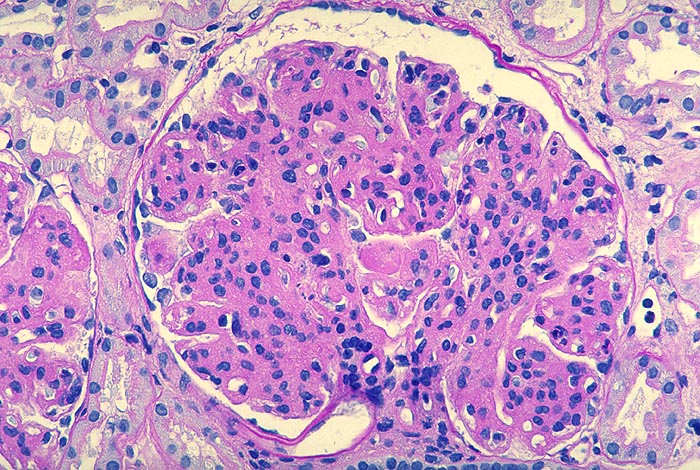

PathoPic – image database / PathoPic ID 2652 - Membranoproliferative Glomerulonephritis: lobuläre Variante

Membranoproliferative Glomerulonephritis: lobuläre Variante

Starke mesangiale Sklerose und ausgeprägte mesangiale Hyperzellularität. Die peripheren Kapillarwände sind stark verdickt. Stellenweise lässt sich eine mesangiale Interposition vermuten. Im Zentrum finden sich Kapillarschlingen, die durch plumpe Proteindepots nahezu vollständig verschlossen sind.

Phasischer Ablauf:

Initial finden sich in den Schlingen subendotheliale Immundepots begleitet von gelapptkernigen Leukozyten und Monozyten.

Mit Abnahme der endokapillären Hyperzellularität kommt es zu einer mesangialen Zellproliferation mit Auswandern der Mesangiumzellen in die Peripherie und Neubildung einer Basalmembran (mesangiale Interposition).

Schliesslich verschwinden die subendothelialen Depots, die neugebildete Basalmembran wird dicker, die Mesangiumzellzahl nimmt ab und die mesangiale Sklerose zu.